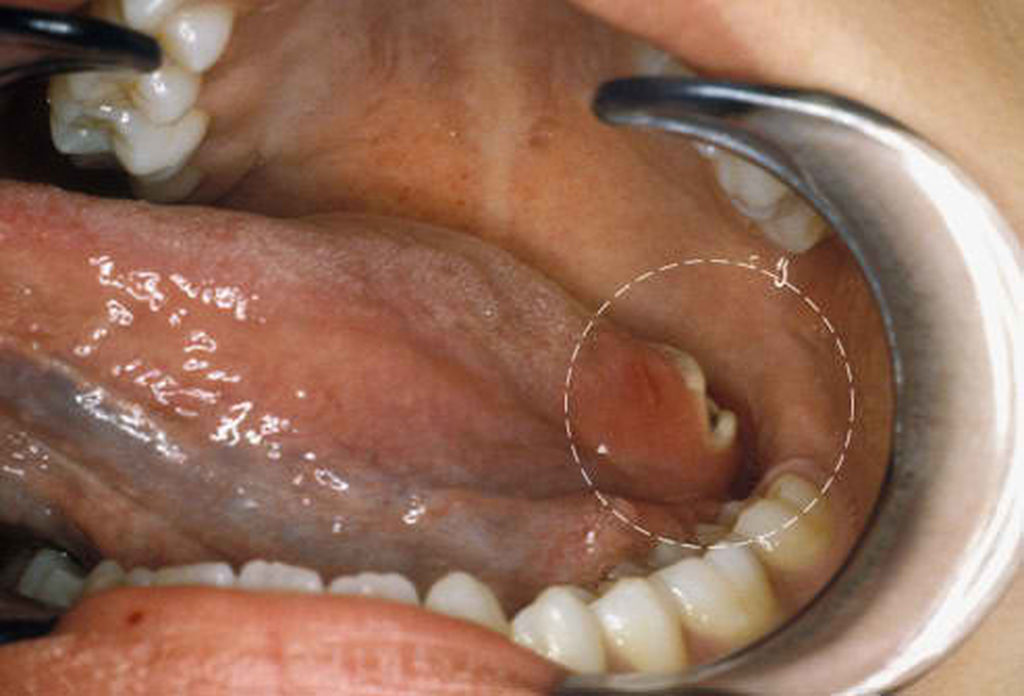

Ο καρκίνος της γλώσσας έχει πολλές μορφές, από τις οποίες η πιο κοινή είναι αυτή που ξεκινά από τα πλακώδη κύτταρα που βρίσκονται στην επιφάνεια της γλώσσας.

– Στη στοματική κοιλότητα: Δηλαδή σε σημείο της γλώσσας που είναι εμφανές και ψηλαφητό. Αυτή η μορφή καρκίνου της γλώσσας διαγιγνώσκεται συνήθως αρκετά νωρίς και αντιμετωπίζεται εύκολα με χειρουργική επέμβαση.

– κόκκινη η λευκή κηλίδα στην επιφάνεια της γλώσσας

– ανοιχτή πληγή (έλκος) στην επιφάνεια της γλώσσας

Στην παρακάτω gallery θα δείτε φωτογραφίες που αποτυπώνουν περιστατικά καρκίνου της γλώσσας.